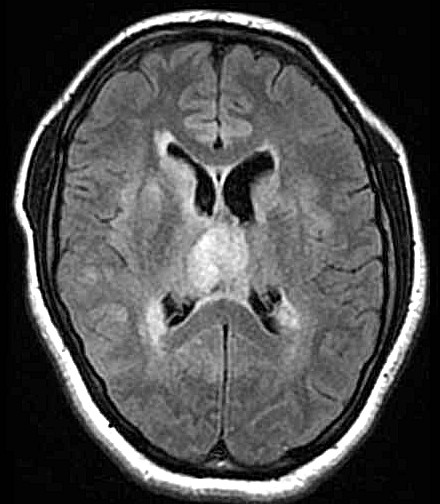

| Fem. 17a. |

| Nódulo sólido homogêneo preenchendo o III ventrículo, com limites precisos, com hipossinal em T1 e hipersinal em T2 e FLAIR, que se impregna por contraste paramagnético. Lesão menor implantada no assoalho do IV ventrículo provavelmente representa disseminação por via liquórica. |

| F. 17a. Tumor teratóide rabdóide atípico de III ventrículo. RM | HE | VIM, GFAP | HHF35, desmina, 1A4 | AE1AE3, EMA |